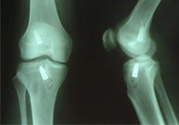

1、部分?jǐn)嗔眩宏P(guān)節(jié)內(nèi)無(wú)積血,外翻位X線(xiàn)片顯示內(nèi)側(cè)關(guān)節(jié)間隙不大,可做局部封閉、彈性繃帶加壓包扎,早期鍛煉股四頭肌或用踝上長(zhǎng)腿石膏托固定于膝內(nèi)翻和稍屈位3—4周,石膏完全干后可開(kāi)始股四頭肌鍛煉和下地行走。

2、完全斷裂:原則上應(yīng)行手術(shù)治療如韌帶斷裂,可直接縫合;如骨附著處撕脫,可用鋼絲貫穿法固定或直接縫合于骨膜及軟組織上。如有撕脫骨片,則用鋼絲或螺絲釘固定。如合并半月軟骨損傷,應(yīng)予以切除。合并前膝交叉韌帶損傷者,應(yīng)先修補(bǔ)。術(shù)后石膏固定4—6周。

4、膝交叉韌帶損傷:前交叉韌帶合并脛骨棘撕脫骨折者,可用膝過(guò)伸和后推脛骨使之復(fù)位,用長(zhǎng)腿石膏固定4—6周。對(duì)于未能復(fù)位者,應(yīng)及時(shí)手術(shù)修補(bǔ)。將骨折片用鋼絲固定。單純韌帶斷裂者,用石膏固定。對(duì)陳舊性損傷,以保守治療為主,經(jīng)鍛煉后,關(guān)節(jié)仍不穩(wěn)定,亦可考慮手術(shù)修補(bǔ)。后交叉韌帶可不修補(bǔ)。